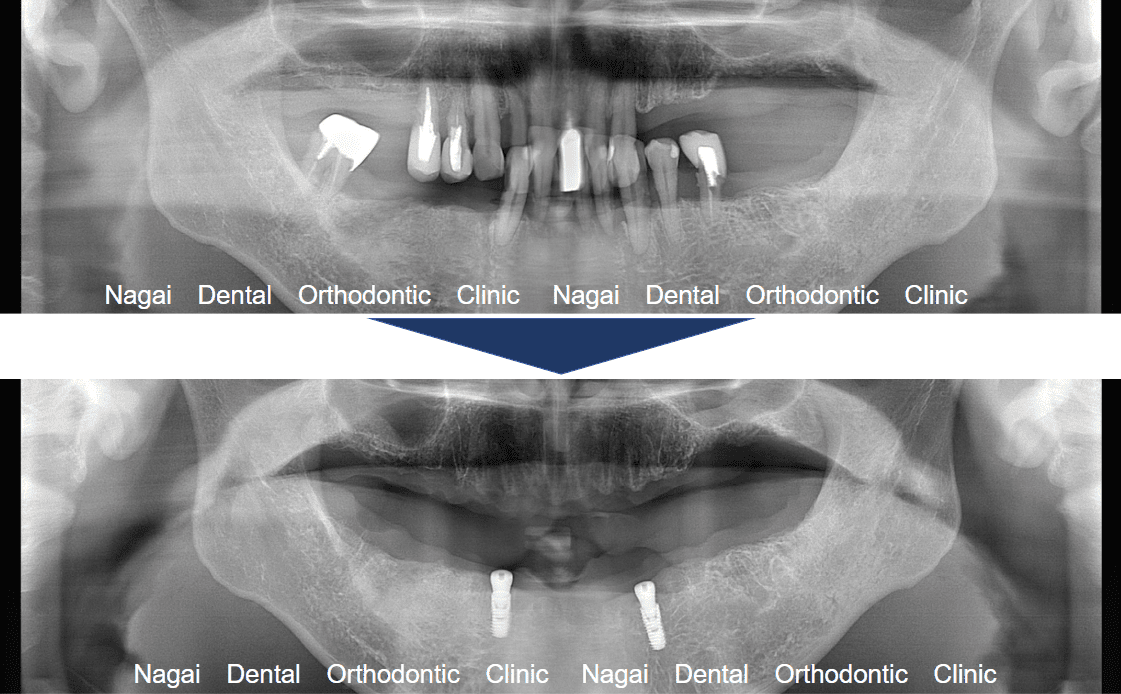

【口腔内の詳細変化】

▲崩壊していた咬合関係を根本から再構築しました

▲支持の安定が期待される治療を行いました

| 治療内容 | 上顎:ドイツ式入れ歯 |

|---|---|

| 年齢/性別 | 40代/男性 |

| 背景 | 重度歯周病と義歯の不適合により、歯列が乱れ、咬合(噛み合わせ)が著しく崩壊した状態で来院されました。当院では上下顎への精密なアプローチを選択し、不適合な義歯による粘膜の炎症や咀嚼困難を解消。崩壊していた咬合関係を根本から再構築しました。術後は、40代という年齢に相応しい健康的で美しい歯並びと、心地よく噛める機能を改善。審美・機能両面の回復により、生活の質が大きく向上しています。 |

| 治療期間 | 約1年(通院15回) |

| 費用 | 1,650,000円~4,950,000円(税込) |

| リスク/副作用 | インプラント手術は全身状態や持病によっては適応できない場合があります。また、術後の口腔清掃を怠ると、天然歯の歯周病に似たインプラント周囲炎が起こる可能性があるため、定期的なメンテナンスが必要です。 |